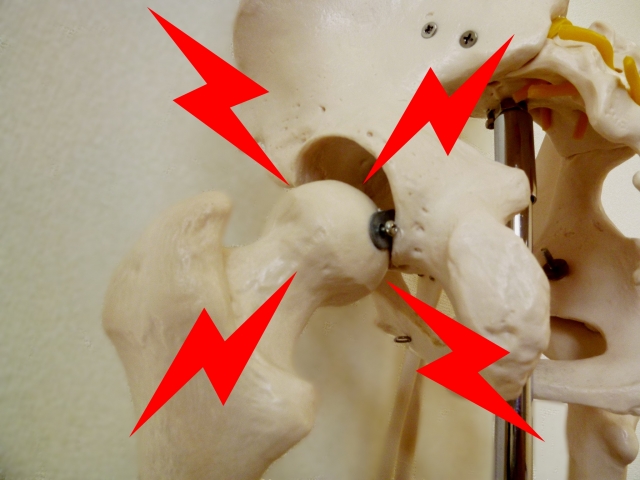

先天性股関節脱臼とは・・・

先天性股関節脱臼とは、いったいどんなものなのか・・・。

この先天性股関節脱臼という病気は、大腿骨部分と骨盤の接触部分の正しい位置になく、ズレが生じることによって歩き方に影響を及ぼすと言われている病気です。

くぼみを形成している寛骨臼といわれる部分に大腿骨の上部がこの丸み(くぼみ)にはまらないことで、この病気と診断されるケースがあります。

先天性と言われ、遺伝的な影響が最も強い説がありますが、実際にはそうでないようで、後天的にもこの病気は発症するものであり、特に生まれて間もなく生後においてこの骨の位置関係にズレが生まれてくることもあります。

そのため、早い段階でこの股関節の位置を正しい位置に調整する必要性がある病です。

現在では、この病名も「発育性股関節形成不全」という言い方で言われることも多いようですね。